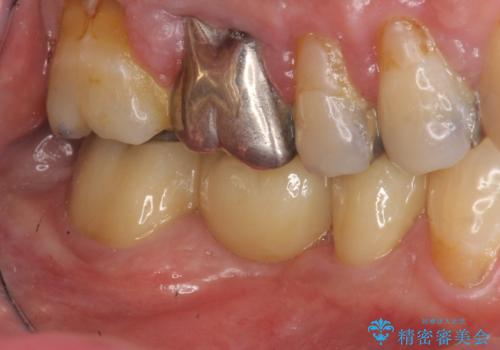

歯の破折 フルジルコニアブリッジ補綴

- 銀歯がダツリし、支える歯が破れている状態で抜歯を余儀なくされました。

短期間での咬合昨日の回復、手術を希望されなかったのでブリッジによる咬合機能回復を計画します。

かみ合わせが強いのでフルジルコニアクラウンベレッツァを用いたブリッジを製作。

- 24万円(仮歯・フルジルコニアクラウン×3)費用は治療当時の料金となります